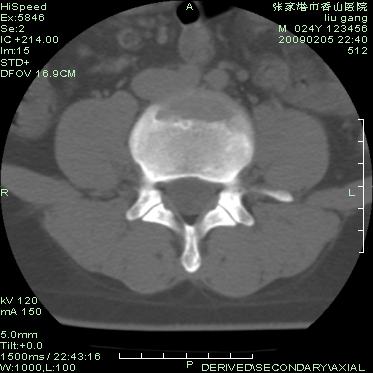

以下是引用随光逐影在2009-3-11 14:43:00的发言:[br]平片:l3、4、5及s1前上缘见类似“切角征”。[br]ct扫描:腰椎多个节段椎间盘向椎体内(椎体前部)突出。